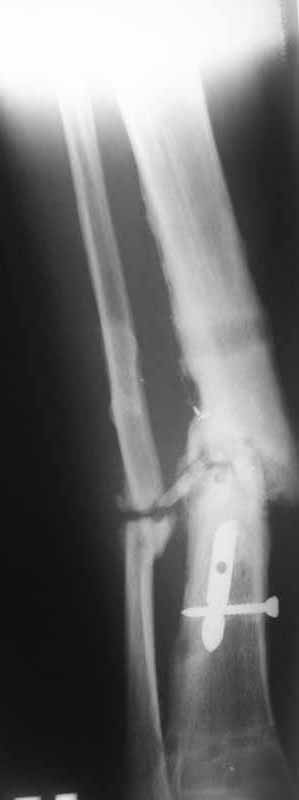

Как-то вот нет уже желания открываться в зоне ложного сустава. Мы бы

попытались сделать закрыто. Винт в дистальном отломке удалить через прокол.

Кусок гвоздя оставить. Новый гвоздь (солидный), возможно с покрытием.

Примерная ситуация. Пациент 37 лет. Синтезировали где-то пластинкой. Попал к нам через 2 месяца.

19 апреля убрали через проколы пластину с винтами, пересекли fibula, наложили аппарат.

Немного потянули по оси, убрали вальгус, ротацию. 22 апреля (на 3-е сутки) заштифтовали окончательно. 29 апреля выписали из отделения. На все ушло 10 дней.

С уважением, Никита Заднепровский